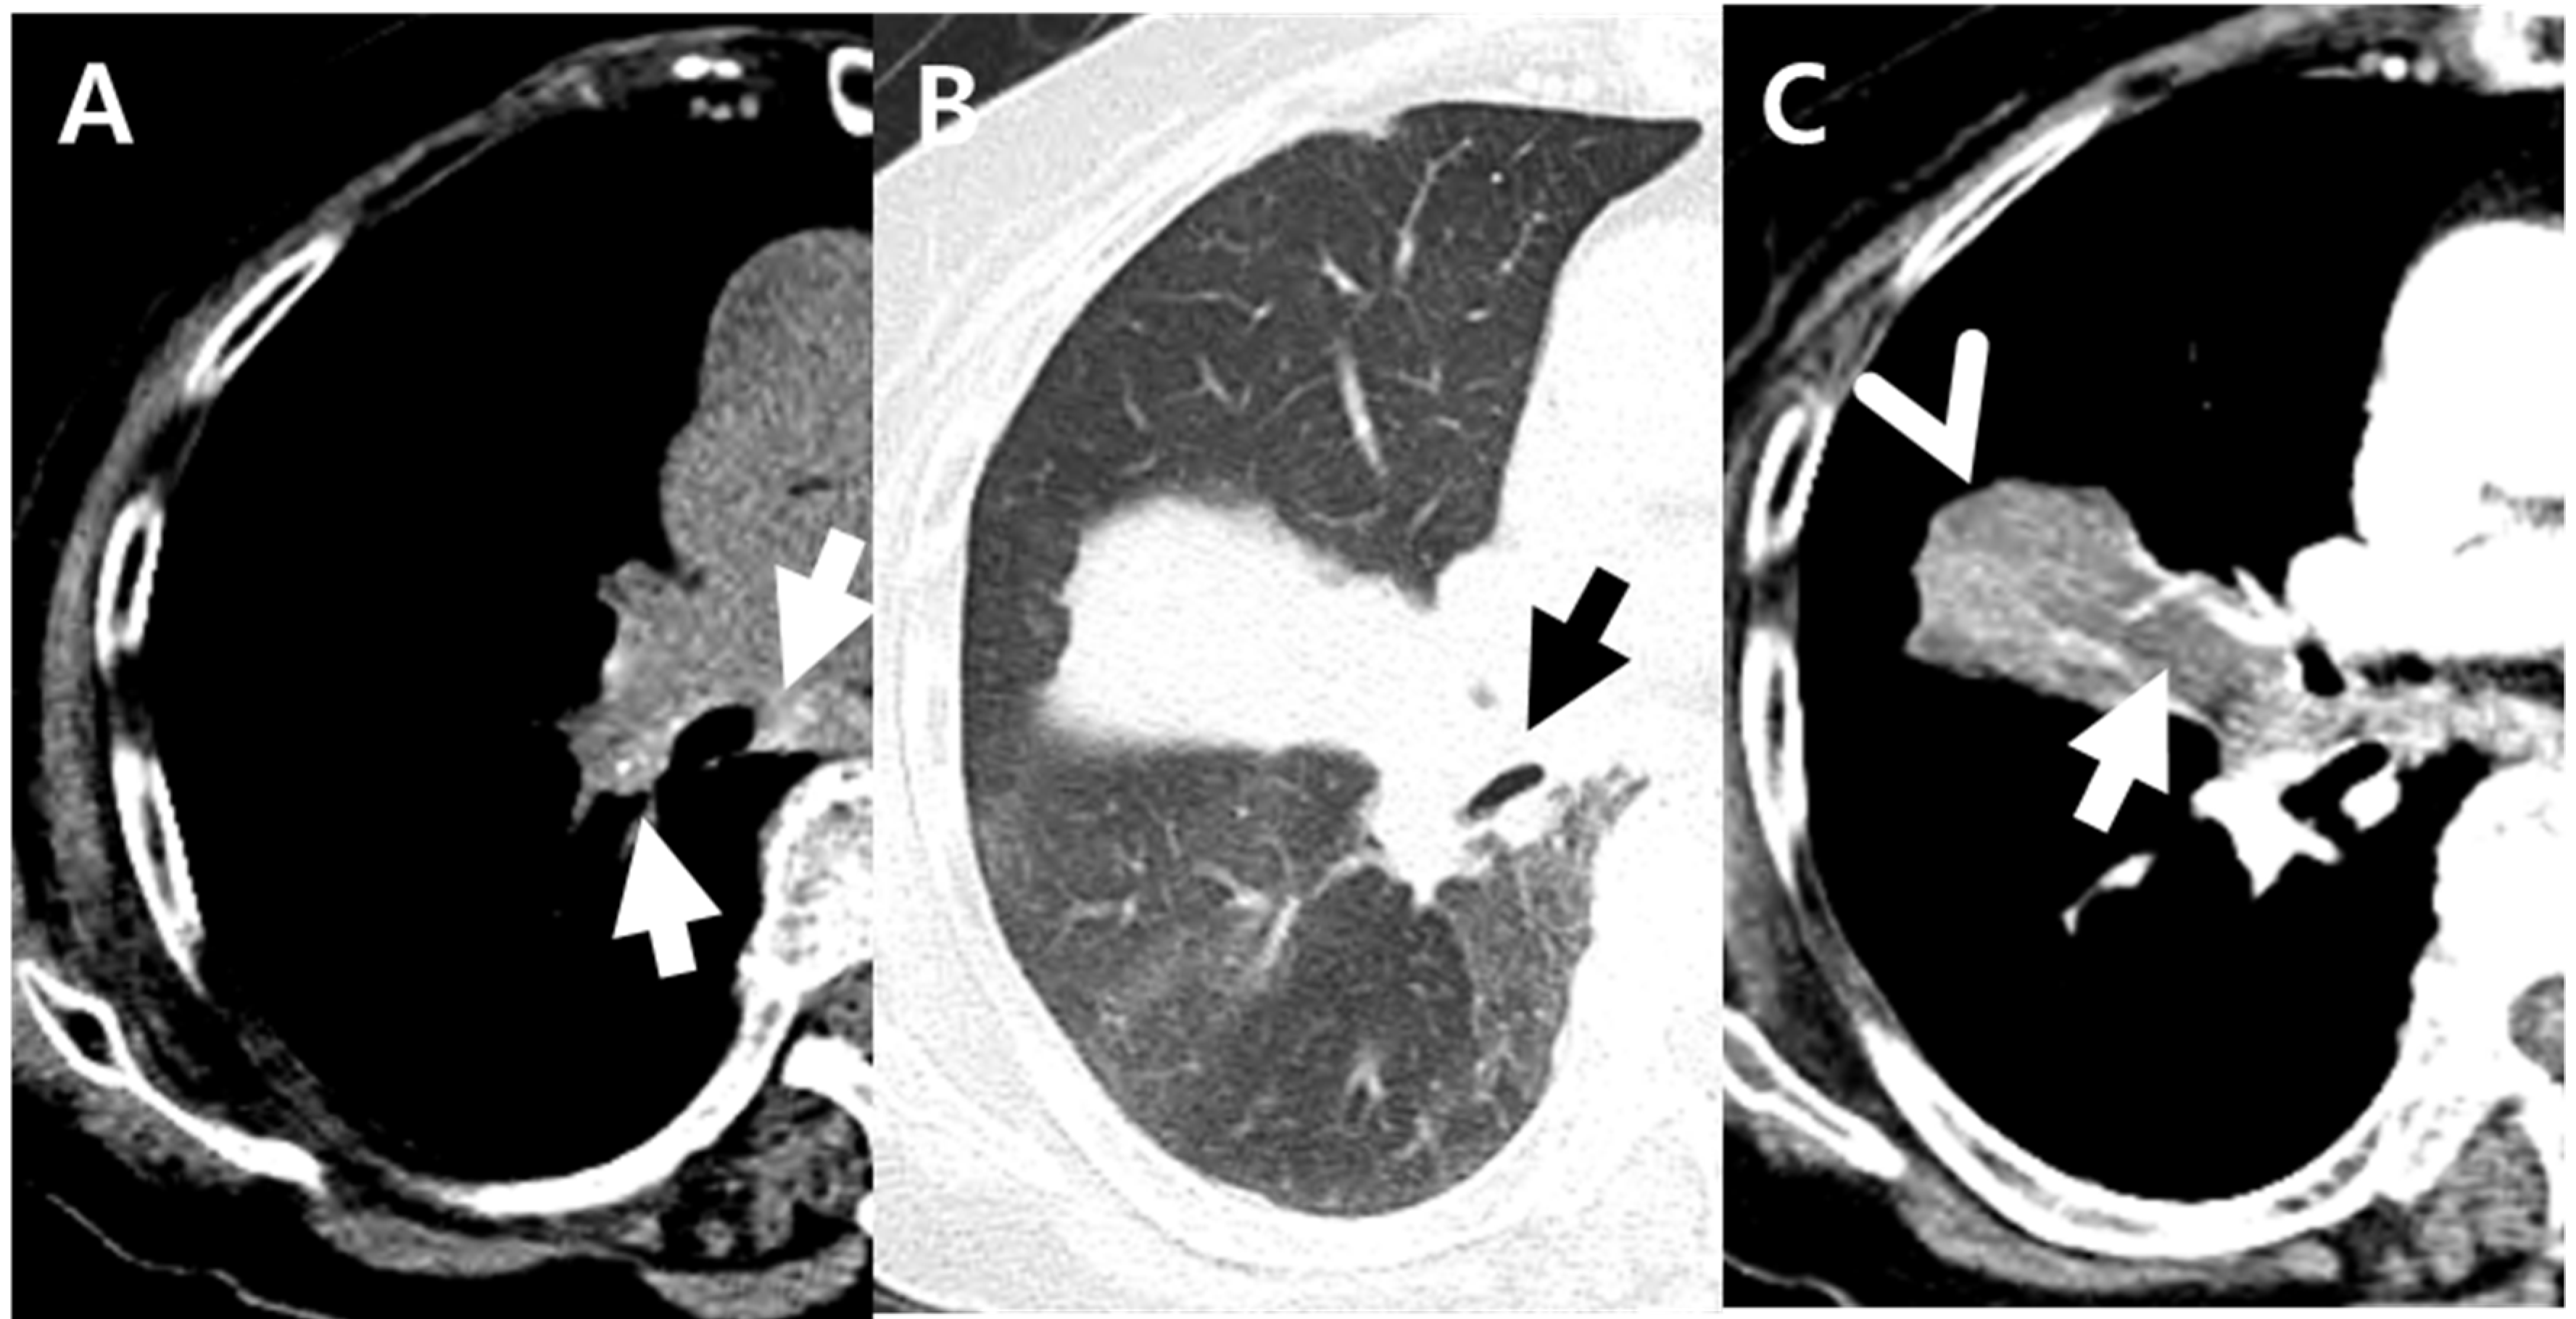

| Internal low-density area or focal contour bulge within atelectasis | 20 (10%) | 18 (64%) | 2 (1%) | <0.001 *** |